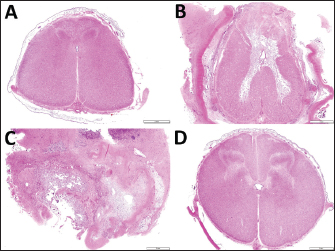

On the cut surface of the resected mass, a tubular structure was seen to run within the center of the mass parenchyma (Fig. 4A). In the tubular structure, a 2–3 mm thick, white, cartilage-like outer structure formed an empty, rounded lumen measuring approximately 1 cm in diameter, surrounded by this outer structure. This macroscopic feature of this tubular structure resembled bronchi. The mass parenchyma was macroscopically spongiform. The multiple capsular structures, some pus-filled, were present on the spongiform parenchyma. The mass was fixed in 10% neutral buffered formalin and embedded in paraffin wax. Sections were sliced at 4-micrometer thicknesses, stained by hematoxylin and eosin (HE) staining, and observed under a light microscope. The mass consisted of bronchi-like lumens, large arteries with elastic fibers, lymph node, mixed inflammatory cells, and abundant collagen deposits. The lumens were lined by pseudostratified ciliated epithelial cells and supported by cartilage and muscular layers, consistent with a bronchus. Various-sized vasculature, mature adipocytes, peripheral nerve bundles, edema, fibrin depositions, and hemorrhages were found in connective tissues. Infiltration of macrophages, lymphocytes, and granulocytes were multi-focal to coalescing, and a fragment of sutures was seen with multinucleated giant cells (Fig. 4B). Based on these histopathological findings, the lesion was diagnosed as pyogranulomatous inflammation (suture granuloma) in ectopic tissue.

Histopathological examination revealed a loss of their normal histological structure at the locations of the L1 and L2 (Fig. 5). The histopathological abnormalities included extensive necrosis (malacia) in the gray matter, diffuse white matter degeneration with axonal swelling (spheroids), and gliosis and scarring of the dorsal part of the spinal cord, including the dorsal funiculus (Fig. 4C, D). The dura mater was thickened diffusely due to fibrous scar tissue formation. Based on clinical and histopathological examination results, the destructive changes of the gray matter accompanied by neuron loss were considered to contribute to the irreversible development of hindlimb paralysis. The degenerative changes within the white matter might also be a secondary change.

Fig. 4. The cut surface of the resected mass (A) showing a bronchi-like structure in the center of the spongiform parenchyma, including multiple pus-filled capsular structures. (B) Histopathology of a part of the resected mass. Granulomatous inflammation with a cross-section of sutures (left upper side) and some multinucleated giant cells (arrowheads). Capsulation by fibroblasts and neovascularization are also noted. HE, Bar, 50 µm. Histopathological images of the ventral horn (C) and the ventral funiculus (D) of the first lumbar spinal cord in the specimen obtained at autopsy. (C) Extensive necrosis (malacia) is seen in the gray matter, where no neuron is observable, with infiltration of fat granule cells. HE. Bar, 100 µm. (D) Swelling of the axon (spheroid) and vacuolization in the myelin sheath are seen. HE. Bar, 50 µm.

Fig. 5. Transverse section images of the spinal cords at the locations of the thirteenth thoracic vertebra (A) and the first, second and fourth lumbar vertebras (B, C and D, respectively). (A) Degeneration of the white matter is seen diffusely in the dorsal funiculus and sporadically in the ventral funiculus and the lateral funiculus. (B) Extensive malacia is seen within the gray matter. (C) The spinal cord’s structure is destroyed due to extensive malacia with fibrous scar formation. (D) Degeneration of the white matter is mild. Bar, 2 mm.